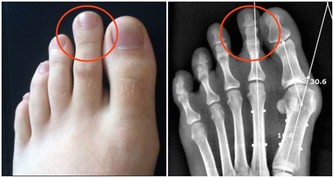

一般腎不好的人都會有早醒的情況,除了這個情況以外還會有腰膝發酸發軟的情況,有些人還會有眩暈的毛病,有些男性還有可能出現遺精的問題,一般這些症狀就是腎虛了。